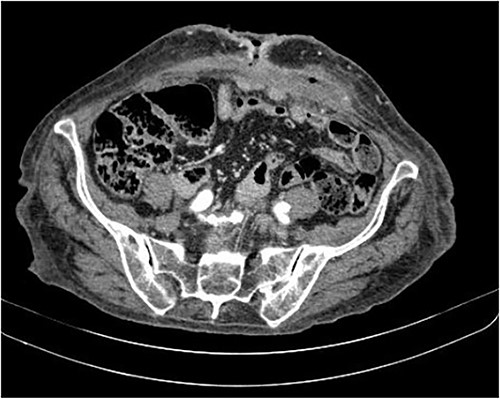

The abdominal computed tomography (CT) scan showed an abscess in the abdominal wall adjacent to the previous mesh, measured 12 × 4.0 × 13.0 cm (Fig. 2). The patient’s laboratory test results showed a mild elevation of protein C-reactive (70.9 mg/L) with normal levels of white blood cells. The patient’s renal function and electrolyte levels were within normal limits.

The axial CT section of the abdomen showing an abscess in the abdominal wall adjacent measured 12 × 4.0 × 13.0 cm.